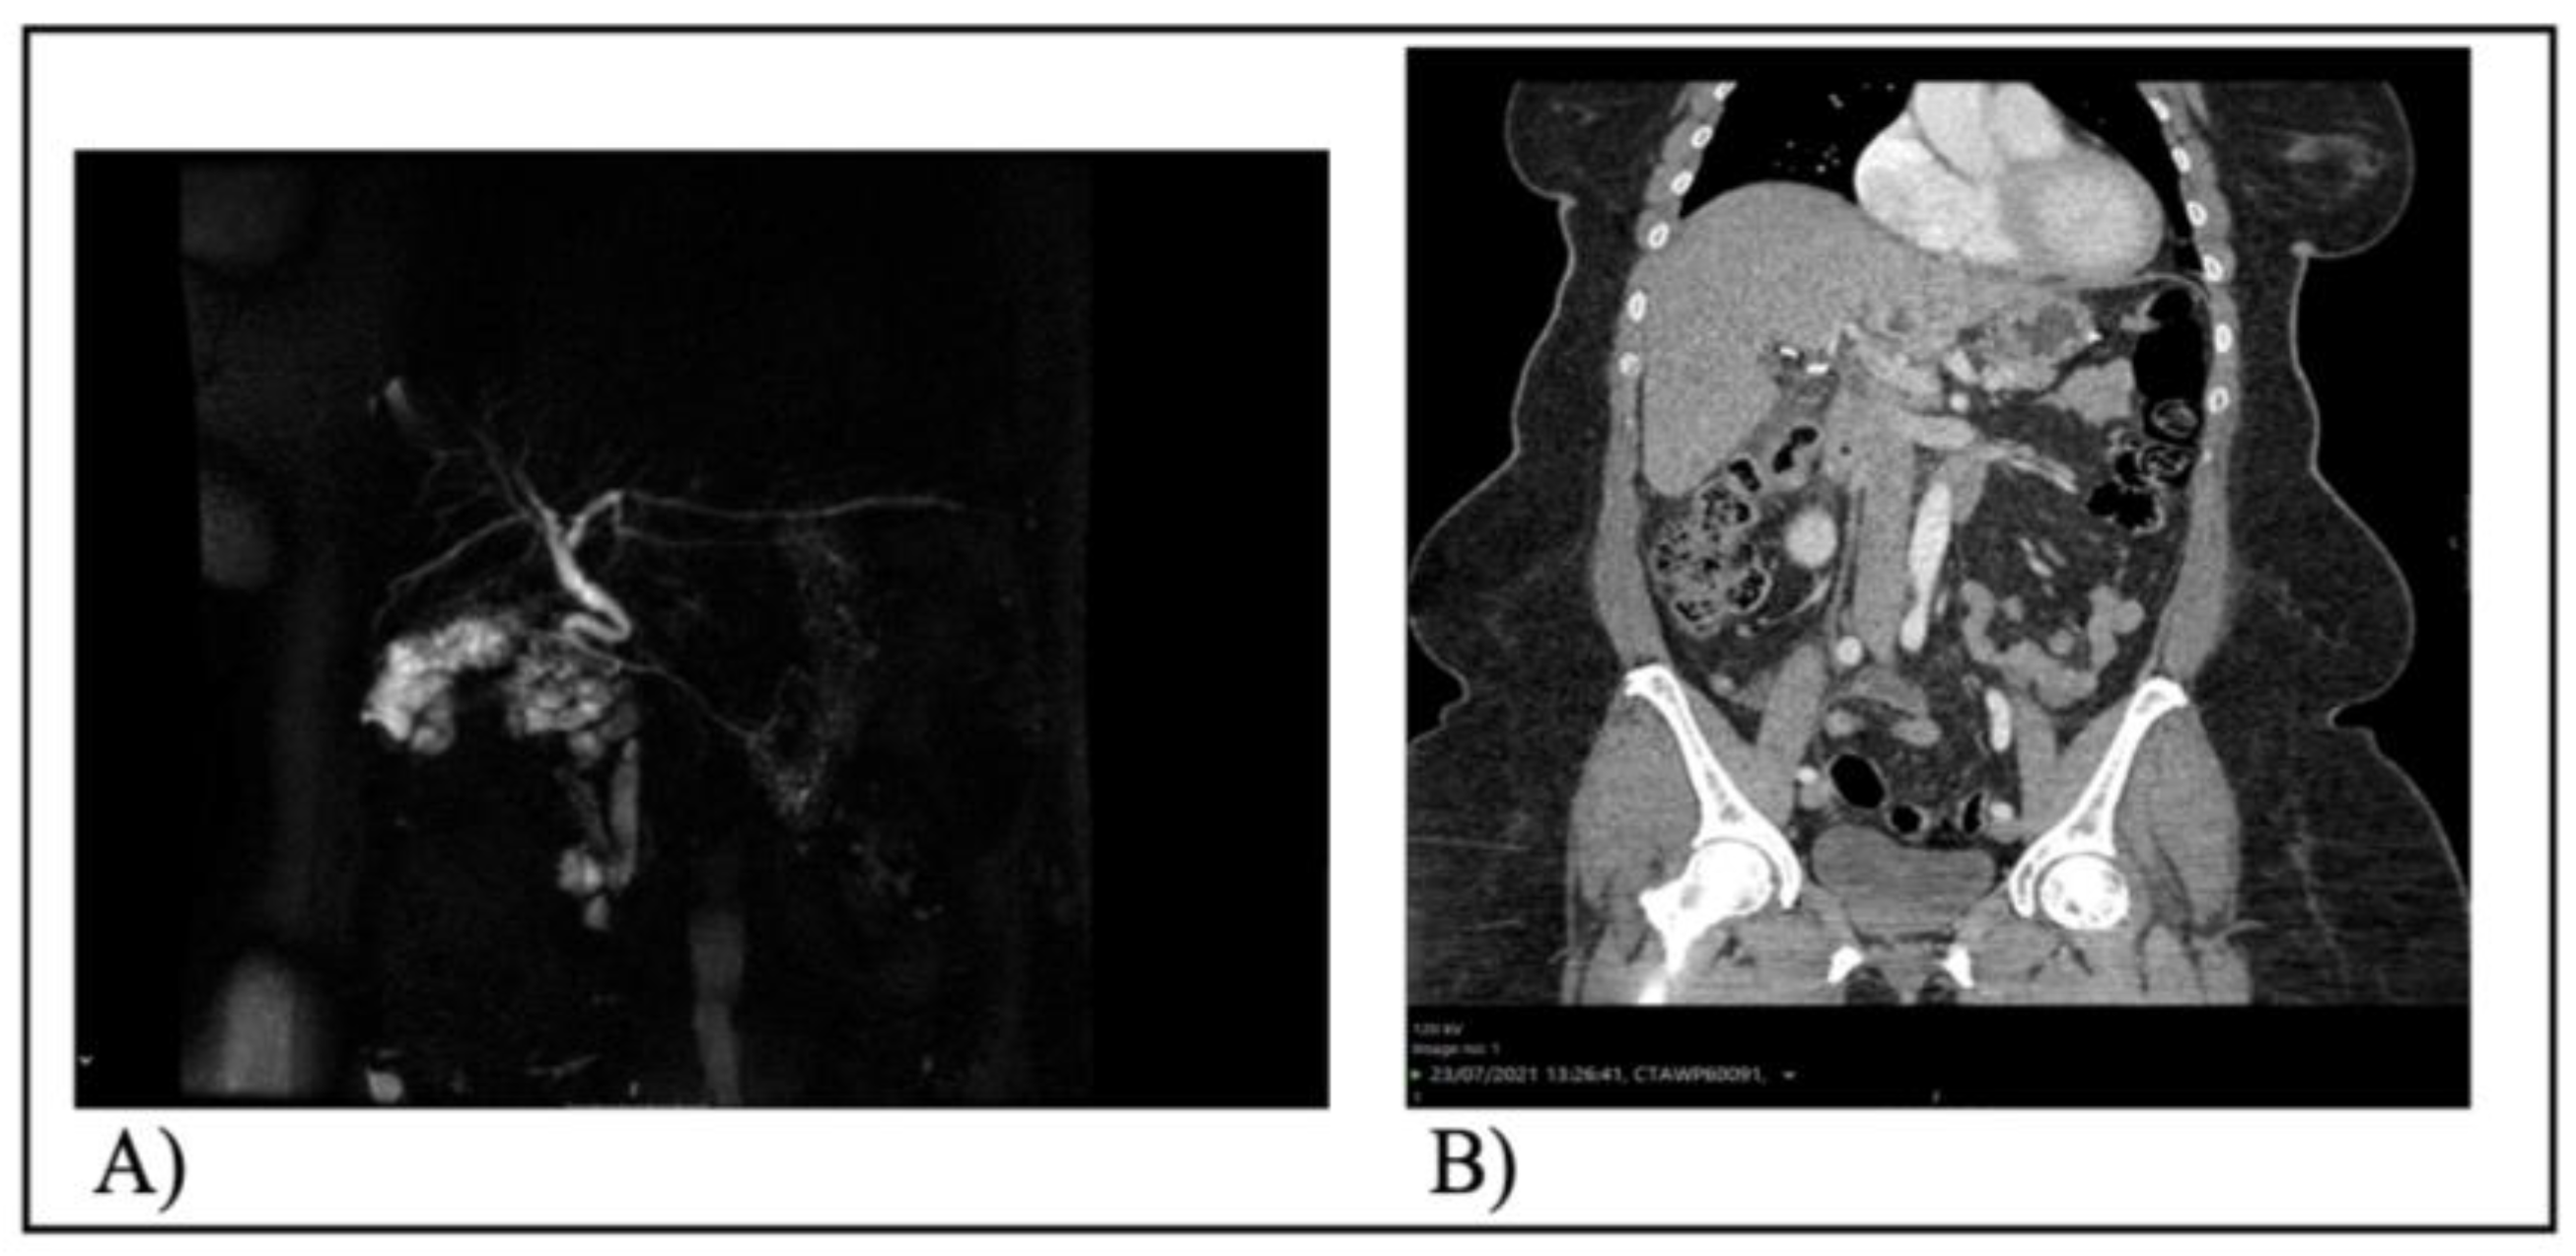

Documentation shows that diagnostic imaging was conducted for all patients to exclude abdominal intra-complications. Neither triple-phase CT scans nor MRCP revealed any pathological findings, including bile duct injuries, injuries to the hepatic artery, or remaining gallstones. Figure 1 features the MRCP of patient 2 and the CT scan of the abdomen for patient 5, which validated the lack of postoperative problems

Figure 1. A) MRCP after laparoscopic cholecystectomy and B) Abdominal CT scan after laparoscopic cholecystectomy. No injuries or other intra-abdominal complication were found after the rise of bilirubin and LFTs in postoperative day 1.